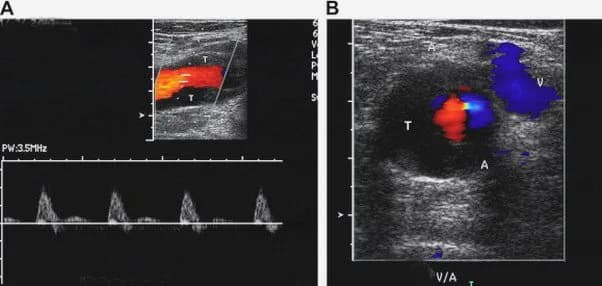

Siêu âm Doppler thường được sử dụng đầu tiên để chẩn đoán huyết khối tĩnh mạch sâu, với độ nhạy 96% và độ đặc hiệu 98% ở các đoạn gần (từ tĩnh mạch vùng khoeo trở lên vùng chậu). Chụp tĩnh mạch cản quang được xem là tiêu chuẩn vàng để chẩn đoán huyết khối tĩnh mạch sâu, nhưng chỉ được sử dụng khi nghi ngờ lâm sàng cao mà kết quả siêu âm Doppler âm tính. Xét nghiệm D-dimer (chất giáng hóa fibrin) có giá trị tiên đoán âm tính tốt, và thường được sử dụng để loại trừ chẩn đoán ở bệnh nhân có nguy cơ thấp huyết khối tĩnh mạch sâu.